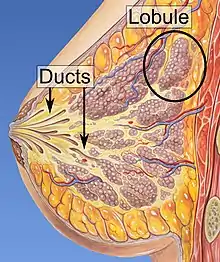

| Lobules of the mammary glands. | |

Invasive lobular carcinoma (ILC) is breast cancer arising from the lobules of the mammary glands.[1] It accounts for 5–10% of invasive breast cancer.[2][3] Rare cases of this carcinoma have been diagnosed in men (see male breast cancer).[4]